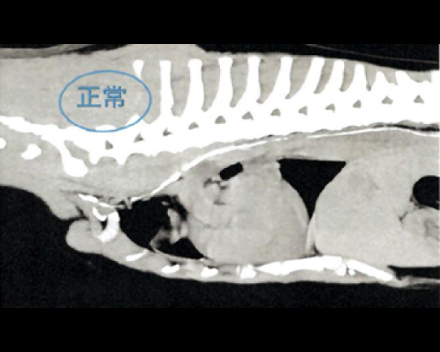

CT検査にて気管の圧迫を確認

内視鏡の位置をCアームで確認し正確に場所の把握が可能